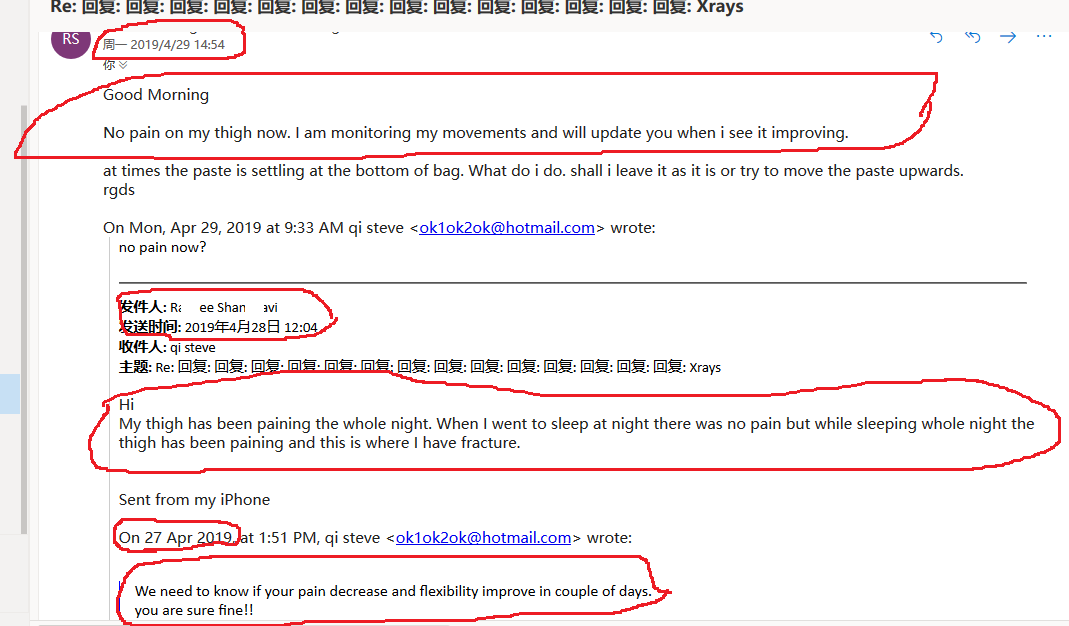

1. The Gentleman in Kenya started his treatment at his home April 27, now he said: (will update his more progresses soon)